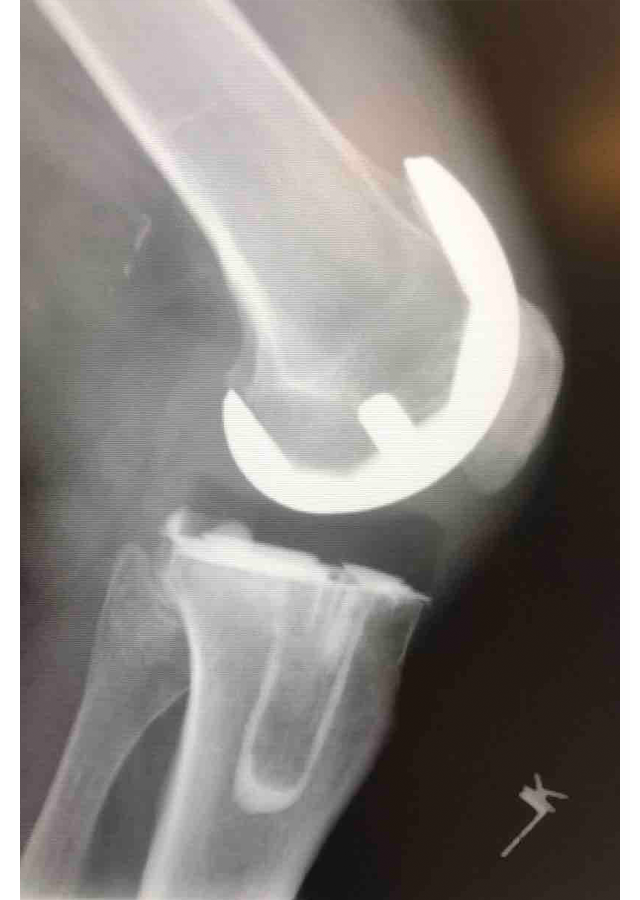

Csípő és térd ízületi betegségek protetizálása

Degeneratívtól, posttraumáson át veleszületett deformitásokig, revíziók, egyszerű és bonyolult helyzetek megoldása.